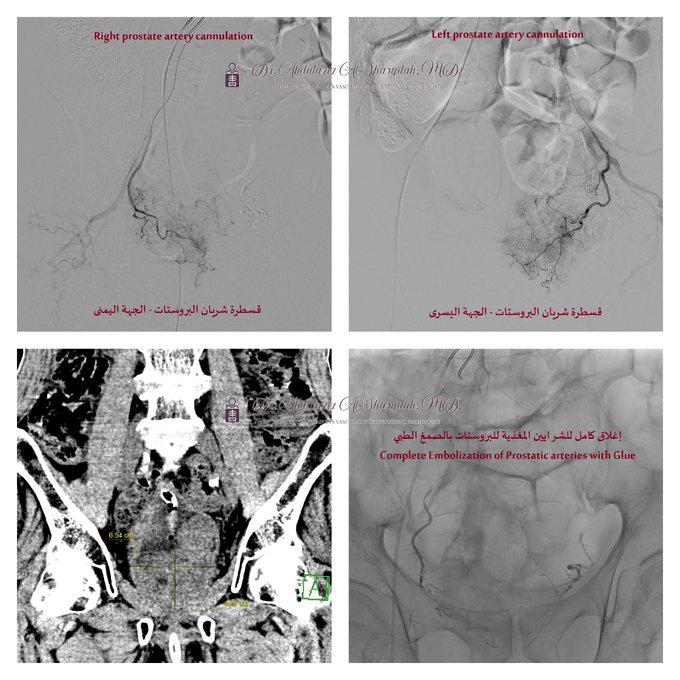

و كشفت الفحوصات الأولية بما في ذلك الأشعة المقطعية للبطن والحوض، وجود تضخم كبير في البروستاتا يضغط على جدار المثانة تم رصده من خلال منظار المثانة تحت إشراف استشاري المسالك البولية د.عبدالله الزهراني والذي تبين وجود تجلطات دموية ونزيف نشط من غدة البروستاتا، مما استدعى تدخلاً طبيًا عاجلًا بالتعاون مع قسم الأشعة – وحدة الأشعة التداخلية والقسطرة.

و تم إجراء قسطرة لإغلاق الشرايين المغذية للبروستاتا عبر شريان الفخذ باستخدام تقنية الاصمام بالصمغ الطبي تحت التخدير الموضعي، دون الحاجة إلى أي شق جراحي، و هذه التقنية المتقدمة مكنت الفريق الطبي بقيادة استشاري القسطرة والأشعة التداخلية للكبار والأطفال د. عبدالعزيز الشريدة من تحقيق نتائج فعالة وسريعة، حيث شهد المريض تحسنًا كبيرًا في اليوم التالي، وتمكن من التبول بشكل طبيعي دون أي نزيف، مما سمح بخروجه من المستشفى بعد يوم واحد بحالة صحية مستقرة.